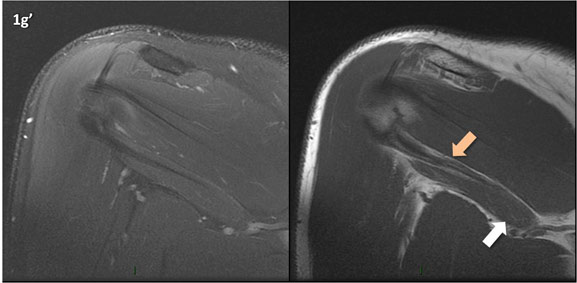

Figura 1 (a-g)': Imagens consecutivas de RM no plano coronal nas ponderações DP com supressão de gordura (DP SG) à esquerda e T1 à direita mostrando . Clique na seta para passar as imagens.

Figuras 1b’ a 1g’ mostrando atrofia da porção superior do músculo redondo menor (seta salmão), com lipossubstituição mais evidente das mais fibras laterais (seta amarela). As fibras mais inferiores e mediais têm atrofia menos evidente.

Repare que estas alterações não são evidentes nas imagens com supressão de gordura.

Chafik et al. também relataram a presença de um pequeno nervo motor acessório em número variável que se insere na porção lateral do músculo redondo menor. O nervo acessório, ao contrário do principal, tem um curso reto e extra-fascial, sendo menos vulnerável aos efeitos compressivos. De fato, nos casos da atrofia parcial do redondo menor, é mais frequente a atrofia da porção mediodorsal com preservação da porção lateroventral, o que poderia ser explicada pela presença do ramo acessório mais lateral do nervo axilar, embora atrofia isolada do componente lateroventral tenha sido reportada em cerca de 17% dos casos de atrofia de apenas uma porção, o que pode ter sido causada por lesão do nervo acessório. No caso do paciente deste mês, a atrofia é mais evidente nesta porção mais lateral e ventral do redondo menor.